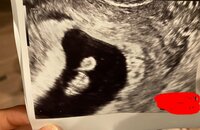

光上は、2日のブログで「昨日YouTubeで発表しましたが、この度第二子を授かりました」と第2子のエコー写真とともに報告。昨年9月26日のブログで第1子女児の出産を報告しており「つい4ヶ月前に出産をしたばかりですが、今、妊娠3ヶ月を迎えようとしています 笑」「産後2ヶ月で妊娠しました つまり私は、1年に2回出産をします!」と説明していた。

この日は「じつは急遽病院行ってきました!!」と報告。「結果何もなかったのですが、妊娠初期って不安が多すぎて」と述べ、「なんかめっちゃ大きくなってらっしゃった!!」と第2子のエコー写真を公開した。